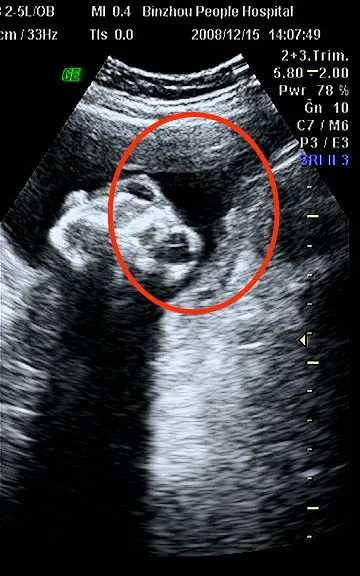

实在不行给我换个医生吧?哈哈哈哈,笑喷了!!!!

医生一边打B超一边百度。孕妇:实在不行给我换个医生吧?哈哈哈哈,笑喷了!!!!